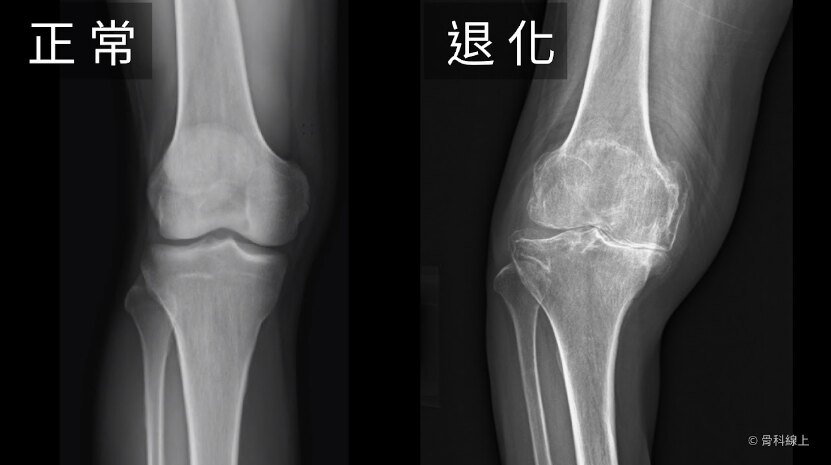

膝關(guān)節(jié)骨關(guān)節(jié)炎是以膝關(guān)節(jié)軟骨退變和骨質(zhì)增生為特征的疾病,隨著病情進(jìn)展,軟骨退變(如:磨損)越來(lái)越嚴(yán)重,逐漸出現(xiàn)關(guān)節(jié)疼痛、腫脹、僵硬、活動(dòng)受限乃至畸形(O型腿、X型腿、屈曲攣縮畸形等)。如下圖所示,膝關(guān)節(jié)骨關(guān)節(jié)炎的進(jìn)展與軟骨磨損密切相關(guān):膝關(guān)節(jié)骨關(guān)節(jié)炎的典型表現(xiàn)為:1、關(guān)節(jié)疼痛腫脹:疾病早期膝關(guān)節(jié)疼痛較輕微,常可休息后緩解或口服止疼藥后緩解。隨著疾病進(jìn)展疼痛逐漸加重,休息或止疼藥治療效果有限,甚至休息/睡眠時(shí)膝關(guān)節(jié)仍舊疼痛(靜息痛),同時(shí)伴隨膝關(guān)節(jié)腫脹??蓛蓚?cè)膝關(guān)節(jié)同時(shí)發(fā)病,也可能癥狀一側(cè)較重、一側(cè)較輕;2、關(guān)節(jié)僵硬:患者在晨起或久坐、久站后,變換體位或姿勢(shì)時(shí)膝關(guān)節(jié)會(huì)出現(xiàn)活動(dòng)不利、僵硬感,需要慢慢“活動(dòng)開(kāi)”后,僵硬感才會(huì)逐漸減輕;3、關(guān)節(jié)活動(dòng)受限:當(dāng)膝關(guān)節(jié)骨關(guān)節(jié)炎逐漸進(jìn)展至晚期,膝關(guān)節(jié)僵硬感逐漸加重,隨著軟骨磨損與骨質(zhì)增生,此時(shí)膝關(guān)節(jié)活動(dòng)度與正常(0-135度)相比會(huì)明顯受限,比如無(wú)法完全伸直或者屈曲角度不夠,嚴(yán)重影響膝關(guān)節(jié)功能與患者生活質(zhì)量。如果出現(xiàn)以上這些癥狀,需要及時(shí)到骨科就診,由關(guān)節(jié)外科專家開(kāi)具影像學(xué)檢查并進(jìn)行體格檢查以明確診斷,同時(shí)提供科學(xué)有效的治療方案。(圖片來(lái)源:北京大學(xué)醫(yī)學(xué)部-肌骨課程)